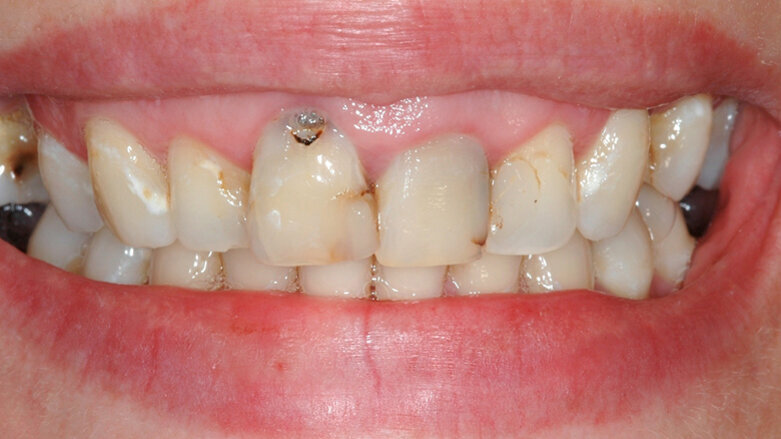

Una giovane paziente di 31 anni, si presenta al mio studio per risolvere l’inestetismo provocato dalla presenza di carie al colletto dell’11, e asimmerie delle parabole. Gli elementi frontali dal 12 al 22 presentavano inoltre diverse carie della corona clinica e contestualmente delle radici trattate in modo incongruo, tanto da provocare delle lesioni endodontiche molto ampie.

Figg. 1, 2 - Situazione iniziale.